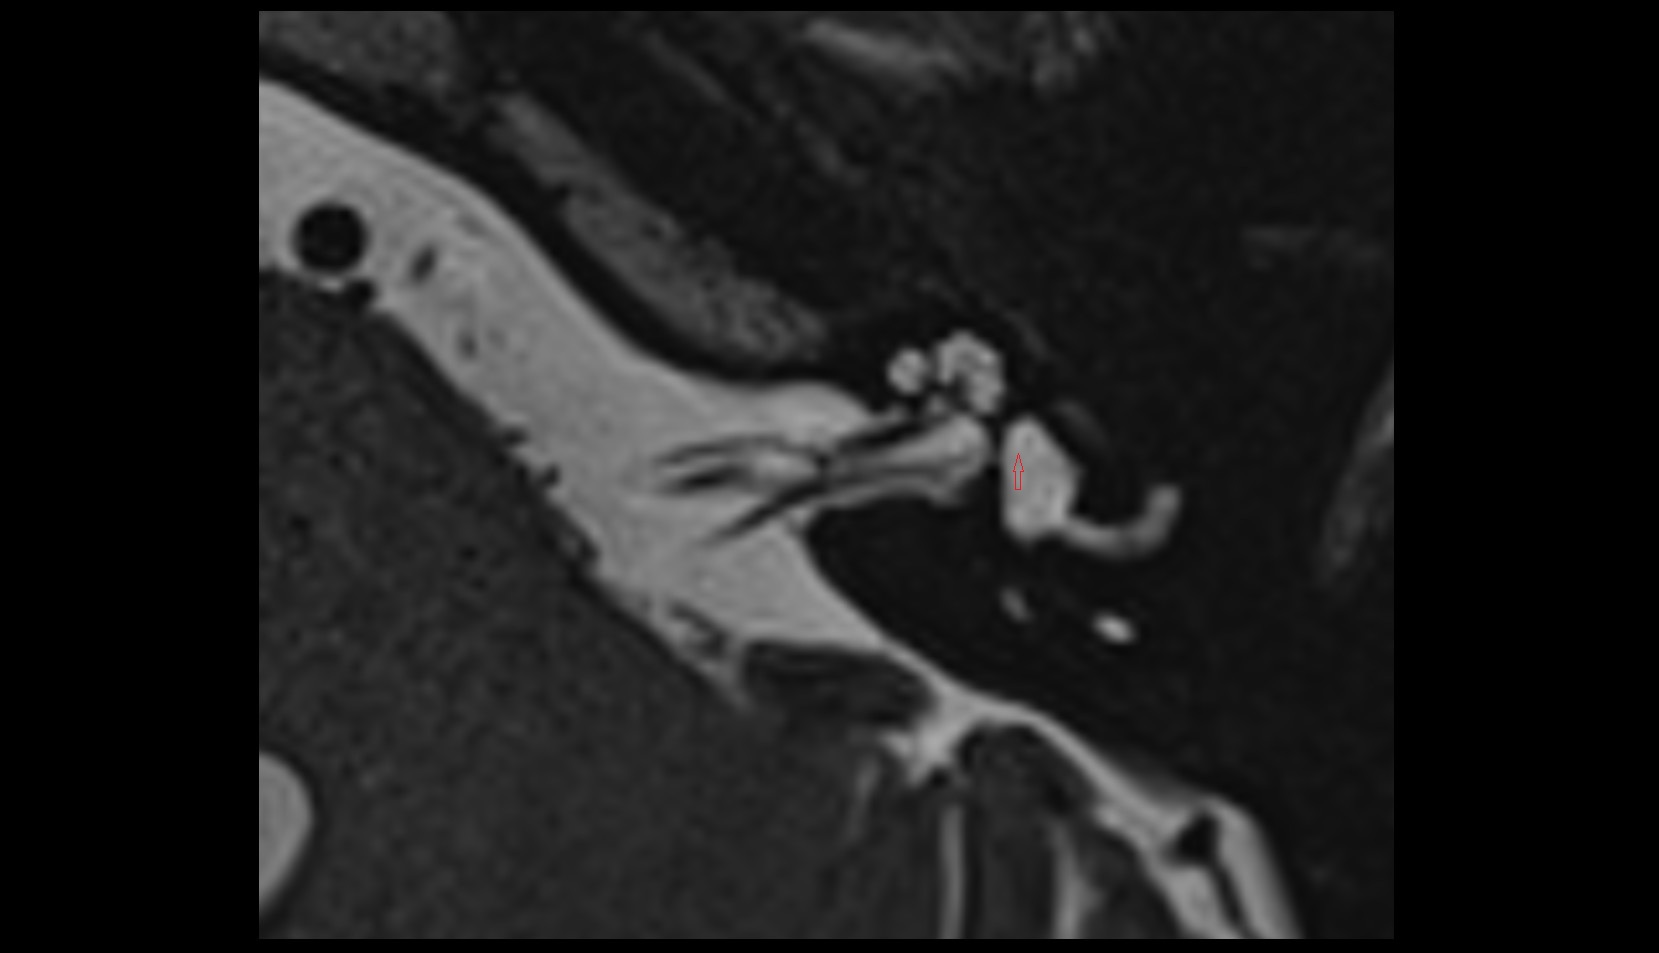

- Temporomandibular joint

- Articular disc of temporomandibular joint

- Articular eminence

- Mandibular condyle

- Mandibular fossa

- Superior head of lateral pterygoid muscle

- Inferior head of lateral pterygoid muscle